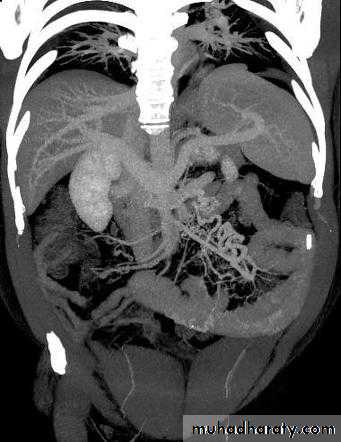

Angiodysplasia

• Angiodysplasia is a degenerative lesion of previously healthy blood vessels found most commonly in the cecum and proximal ascending colon.

• Angiodysplasia is the most common vascular abnormality of the GI tract.

• It is the second leading cause of lower GI bleeding in patients older than 60 years after diverticulosis.

• It may be observed incidentally at colonoscopy in as many as 0.8% of patients older than 50 years.

• These lesions typically are non palpable and small (< 5 mm).

• The prognosis in patients with angiodysplasia is favorable because most angiodysplasias spontaneously cease bleeding (90% of cases).